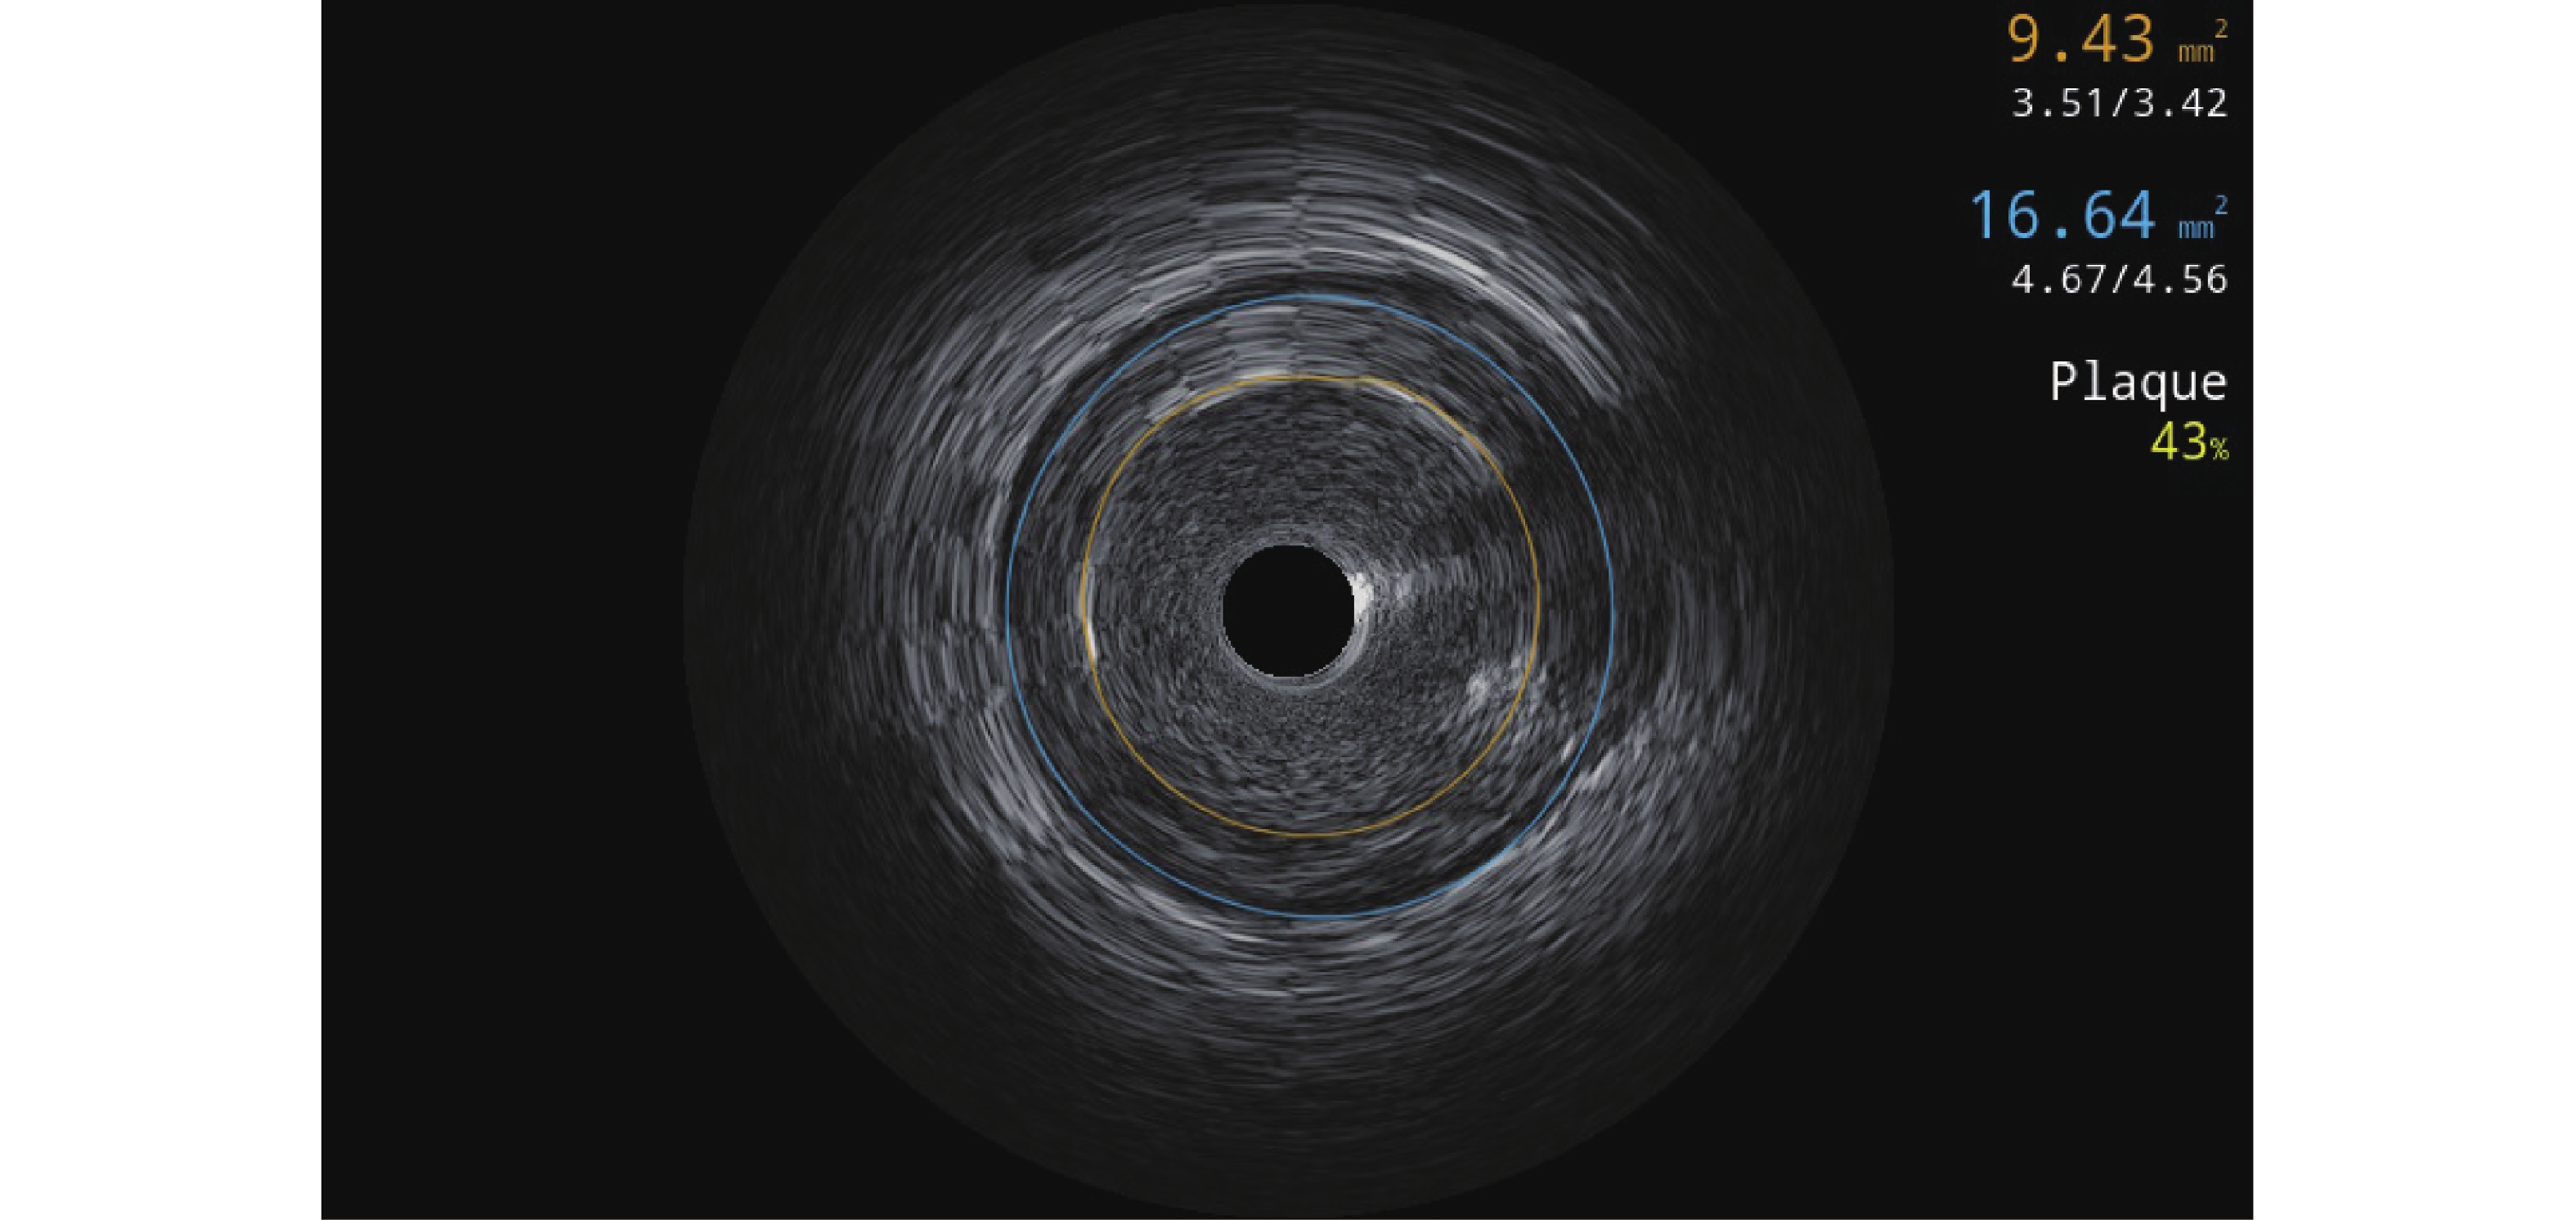

图  2  支架术后Stent Boost支架精显技术+冠脉血管内超声图像

Figure  2.  Stent Boost stent precision display technique+coronary intravascular ultrasound image after stent implantation